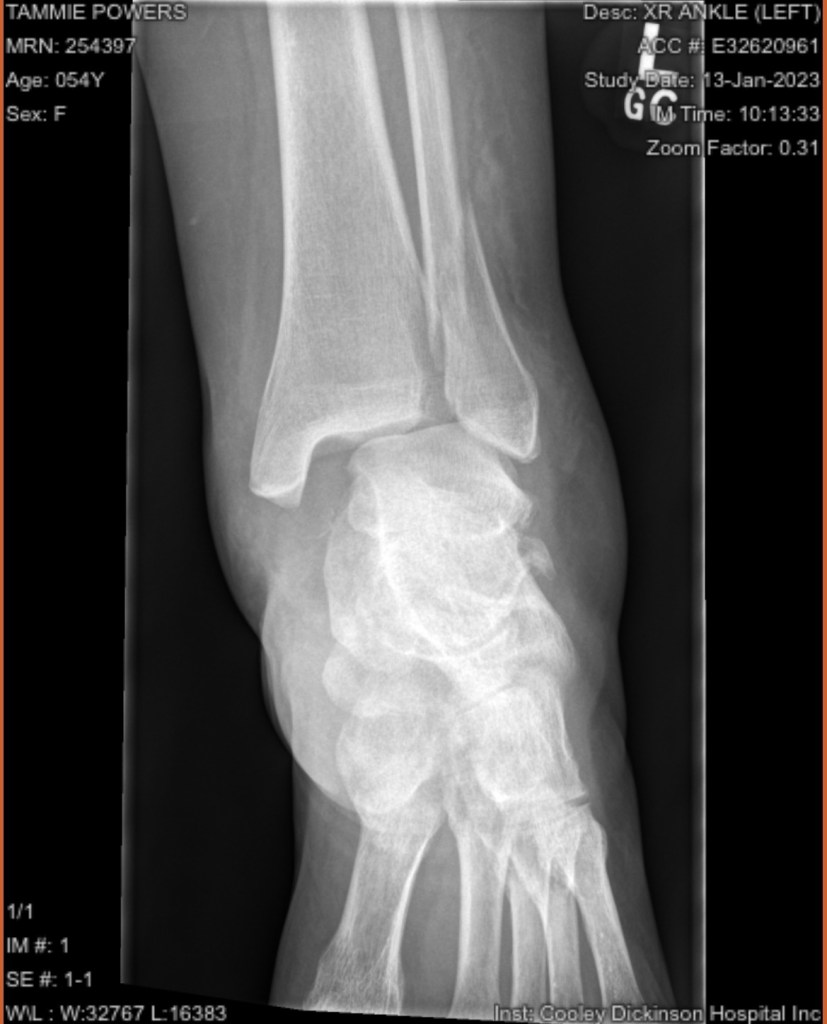

Once I got there they stuck me in a room, and finally did some x-rays. After some prodding they gave me some pain meds, and a diagnosis. A bimalleolar fracture with ligament and tendon damage.

Then came the fun part, a shot of lidocaine in the joint, and 2 doctors reducing the fracture to get it close to the way it was. I went home with pain meds , crutches and instructions to go to Cooley ortho walk in on Monday.

Walk in ortho clinic gave me the results that I expected, but didn’t want. It would be a surgical repair. On January 23, I was at the Kittredge Surgical Center at 6:00 am. My ankle was pinned, plated, the talus was relocated and the ligaments and tendons were repaired. It is likely that the incision went right through my tattoo. So eventually that will need to be repaired as well. I will be non weight bearing for 8-12 weeks, my knee scooter has become my best friend. Because crutches and I don’t get along.